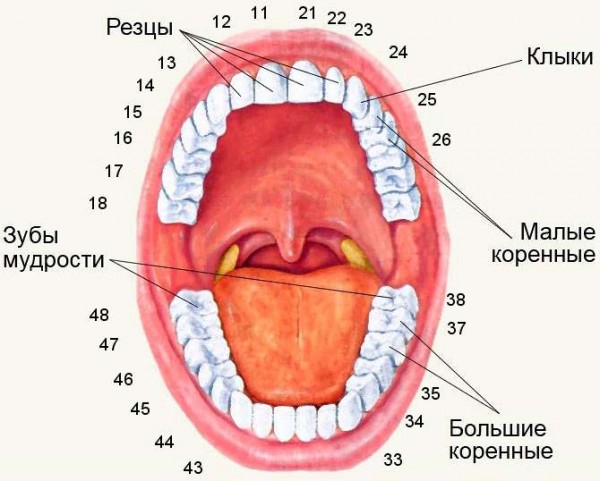

Что делать, если болит зуб мудрости? Что вызывает боль и как с ней бороться? Проблемы с зубами мудрости можно разделить на две категории: прорезывание зуба, а также стоматологические болезни. В первом случае сильно страдает десна, во втором – страдает зуб.

Удаление зубов мудрости проводится с некоторыми нюансами, например женщинам в положении запрещено делать рентген диагностику.